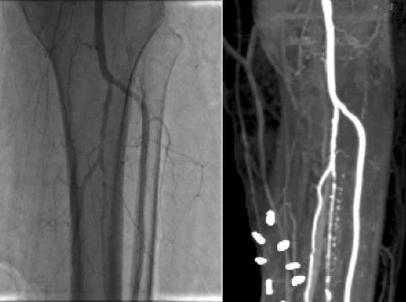

不到60天,溃疡已明显愈合,从治疗后所拍摄的血管造影照片中,可看到鲜明的亮白色动脉条痕。而在注射之前,她的腿几乎没有血液循环可言。干细胞显然已经重建了她大部分已萎缩的循环系统。

这是瓦茉·卡塔夏的血管造影照片,影像显示了她在印度金奈接受实验性干细胞疗法后的腿部已长出静脉,亮白色的条痕就是新的血管。要是疗法没有成功的话,医师就必须切除她的腿。此后,这种成功案例再未出现。血管造影照片显示出她接受实验性干细胞疗法后的腿部已长出静脉,亮白色的条痕就是新的血管。不过,这种成功案例此后再未出现。